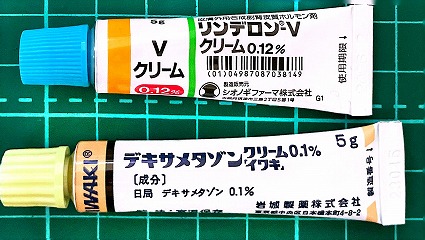

2021.11.13より 西原クリニック 0968-62-0622

2021.04.24 2021.03.06 中垣医院処方箋 =PDF